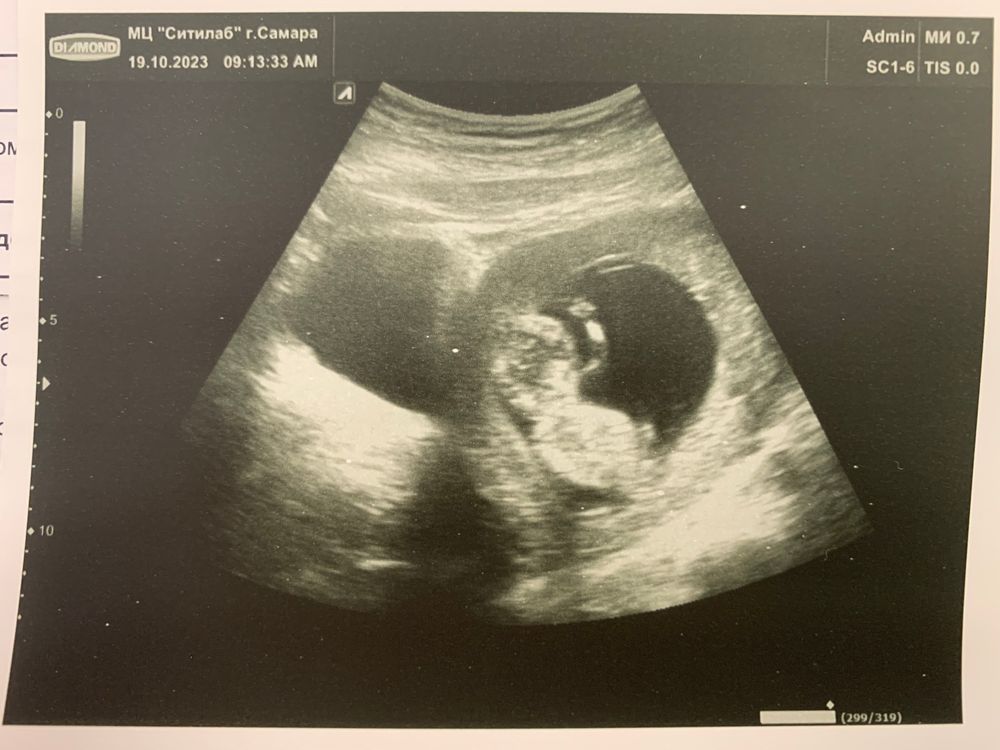

Сегодня в 12н1д сделала 1 скрининг платно. Долго искала клинику, где делают и узи, и анализ крови, нашла. Сначала отправили на узи, потом на сдачу крови.

Узист сначала смотрела трансабдоминальным датчиком, потом трансвагинальным. Я попросила сделать фото и распечатать 🥰

КТР прям по сроку, ПДР сдвигаться не будет, руки, ножки, пальчики, косточки, носик - всё, всё есть!) Затих в момент, когда нужно было суставчики посмотреть, узист попросила меня покашлять, в тот же момент каааак зашевелился. Оказывается, любой мой крик/кашель/чихание вызывает недовольство у бейбика 😅 Ух, как плясал, и руками, и ногами))

ТВП в норме, носовая кость есть, головной мозг четко сформирован по сроку. Животик закрыт. Чсс 165, все кровотоки в порядке, сердце 4-х камерное четко, ШМ 52мм. Плацента по передней и боковой стенке, чуть низковато, но сказали, что поднимется, это нормально пока.